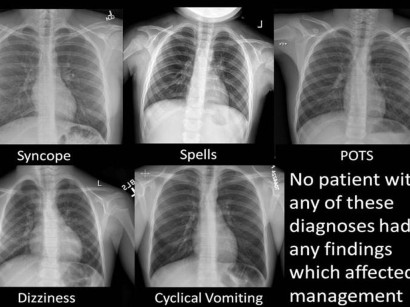

Carus Campus Rontgenbefundkurs Startet Am 22 6 Online Themen Rontgen Thorax Befundung Unterscheidung Von Erguss Infiltrat Stauung Pneumothorax Und Tumoren Unterschiede Im Stehen Und Liegend Thorax Rontgen Abdomen Kompakt Was Kann